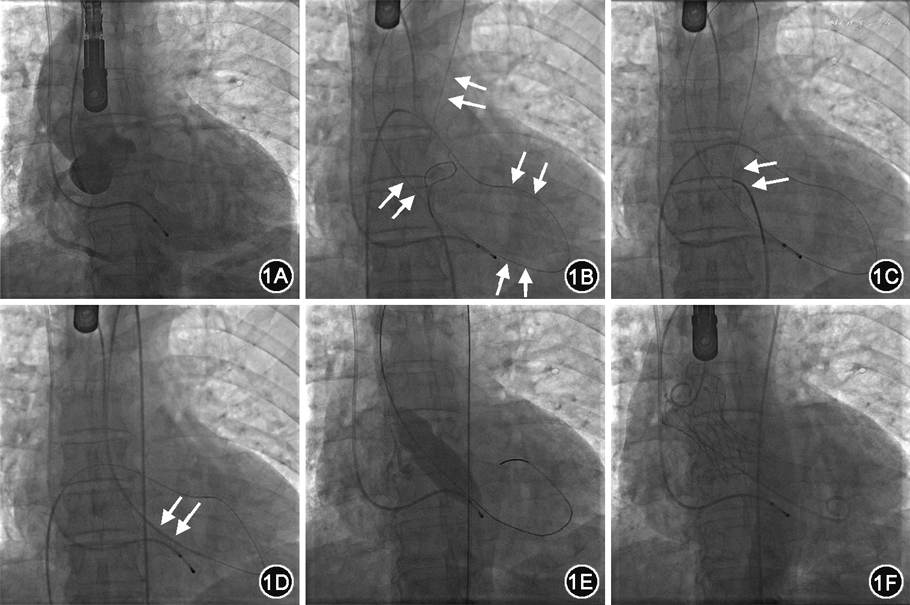

病例1 患者男,65岁,因“胸闷、呼吸困难1个月”入院。既往有阵发性心房颤动、心肌梗死、脑梗死病史。入院体格检查:主动脉瓣听诊区可闻及Ⅲ/6级收缩期喷射样杂音。超声心动图提示:主动脉瓣重度狭窄[瓣口面积0.5 cm2,压力阶差100 mmHg(1 mmHg=0.133 kPa)]并轻度关闭不全,左心室增大(舒张末期内径5.4 cm),左心室收缩功能减低,卵圆孔未闭。诊断为重度主动脉瓣狭窄(aortic valve stenosis,AS),卵圆孔未闭。入院予充分评估,考虑症状与重度AS相关,结合患者病情和家属意愿拟行经导管主动脉瓣植入术(transcatheter aortic valve implantation,TAVI)。全身麻醉下,穿刺右股动脉作为主路,经右股动脉多次尝试送直头及超滑跨瓣导丝,试图跨过狭窄的主动脉瓣进入左心室建立轨道,均未能成功。于是穿刺右股静脉,使用260 cm超滑导丝(日本泰尔冒公司)从右心房经卵圆孔送至左心房、左心室,跨主动脉瓣进入主动脉。再经右股动脉路径,在导丝引导下送入JR 4.0造影导管(美国Merit Medical公司)至降主动脉,经导管送入抓捕器,抓捕从右股静脉顺向送至主动脉的导丝,成功建立轨道,继而行球囊扩张,置入瓣膜,最终完成手术(图1)。